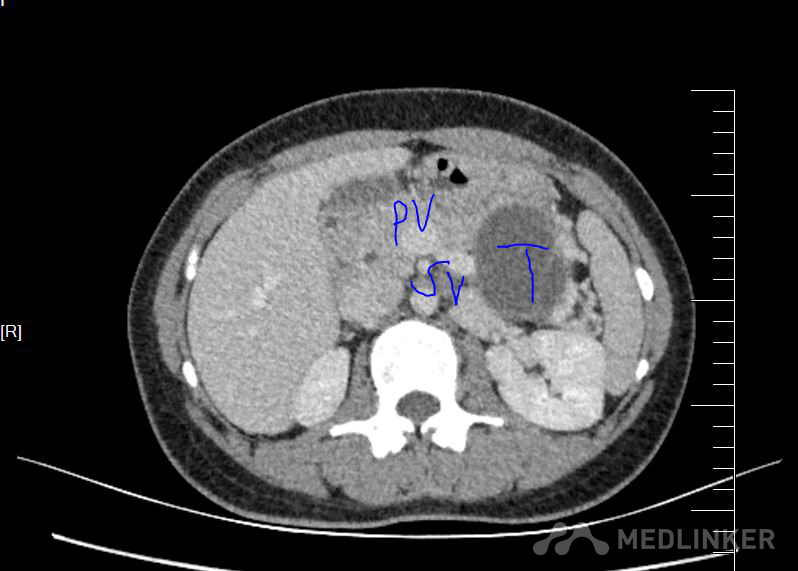

发现胰体尾肿物4个月余 患者4个月前感觉左上腹有包块,行腹部平扫CT示:胰尾区囊性病变,无腹痛,偶有腹胀,无反酸嗳气,无胸闷气短等不适。现为进一步诊治来我科,以“胰腺肿物”收入院,现患者饮食、睡眠尚可,小便正常,近期体重无明显变化。

诊断 胰腺囊性肿瘤 囊腺瘤可能性大,术后病理 粘液性囊腺瘤 治疗 全麻下腹腔镜保脾胰体尾切除

术后恢复顺利,没有出现胰瘘。 胰腺粘液性囊腺瘤由于可能恶变,应该早期手术治疗,传统方式一般开腹手术,由于胰体尾与脾脏灌洗密切,经常需要联合脾脏切除。而脾脏除了具有免疫功能,还有滤血,毁血,储血等功能,故保留脾脏对于患者来讲意义肿大。腹腔镜手术由于独特视角以及放大作用,可以做到保脾胰体尾手术,术中尽量保留脾血管(Kimura手术),如果各种原因,脾血管无法保留,此时仍然可以尝试保脾(Warshaw手术),这时脾脏通过胃血管供血,术后功能良好。